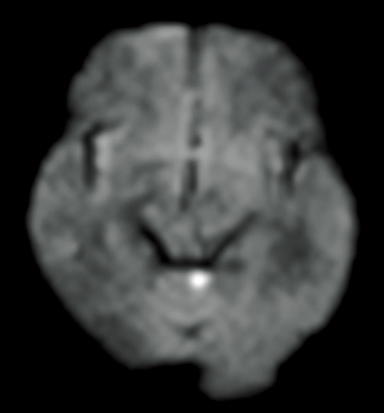

DWI